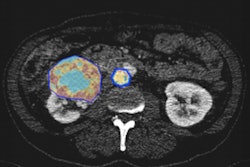

For more complex cases, however, the issue of AI making reliable diagnoses seems less pressing for the moment. Nobody is sure just how far away AI is from making multimodality, multiparametric, or complex MRI diagnoses, but Nikolaou estimates at least 10 years. For example, an algorithm that is trained to detect or even grade prostate cancer from a multiparametric MRI can't differentiate between a significantly higher grade prostate cancer and an inflammation, as it is not trained to do so and does not know about the differential diagnosis of tumor versus inflammation.